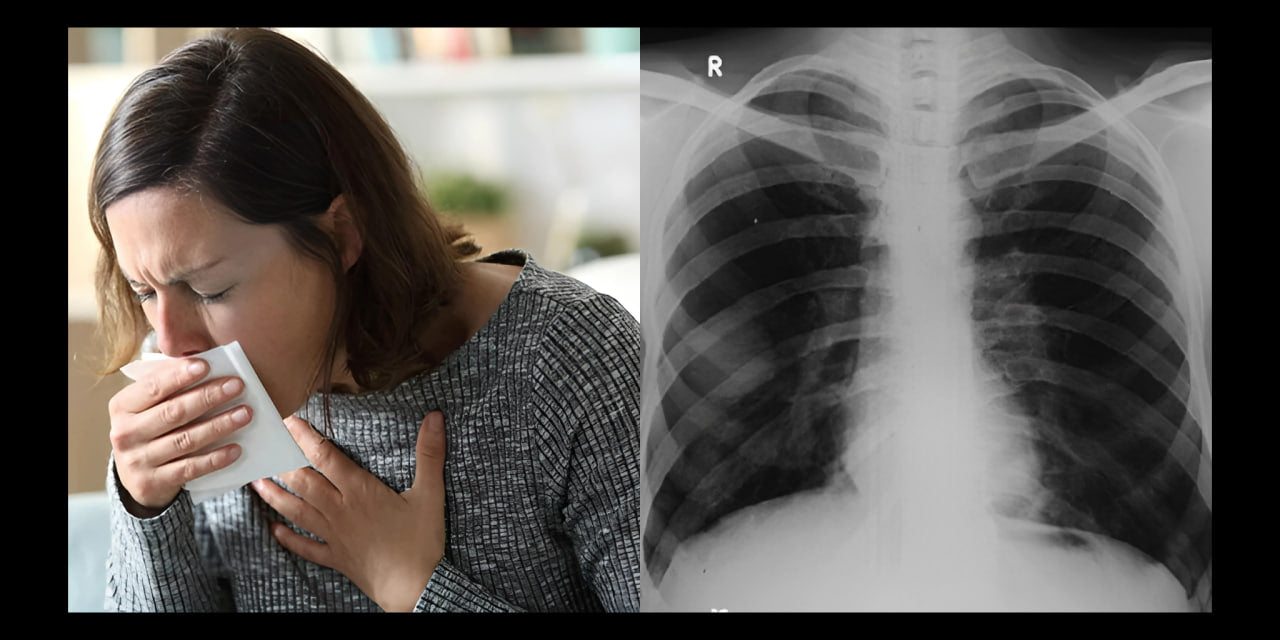

Mijn naam is Francesca van Vught en al ruim 4 jaar heb ik last van hoesten, ademhalingsproblemen en kortademigheid.

Keer op keer kreeg ik te horen dat mijn longen er goed uitzagen en dat ik mij nergens zorgen over hoefde te maken.

Tijdens mijn doktersbezoeken heb ik meerdere malen gehoord dat roken kan leiden tot ernstige longproblemen, waaronder COPD (Chronic Obstructive Pulmonary Disease).

Dit is een progressieve longziekte die de luchtwegen blijvend kan beschadigen, waardoor ademhalen steeds moeilijker wordt.

Ik kwam er zelfs achter dat de Wereldgezondheidsorganisatie voorspelt dat chronische obstructieve longziekte (COPD) in 2030 de derde meest voorkomende doodsoorzaak zal zijn.

Hoewel mijn huidige klachten misschien niet direct wijzen op COPD, werd ik erop gewezen dat roken een risicofactor is die ik niet mag negeren.

Het is iets waar ik zeker rekening mee moest houden, vooral gezien mijn huidige symptomen en de mogelijke gevolgen voor mijn longgezondheid.